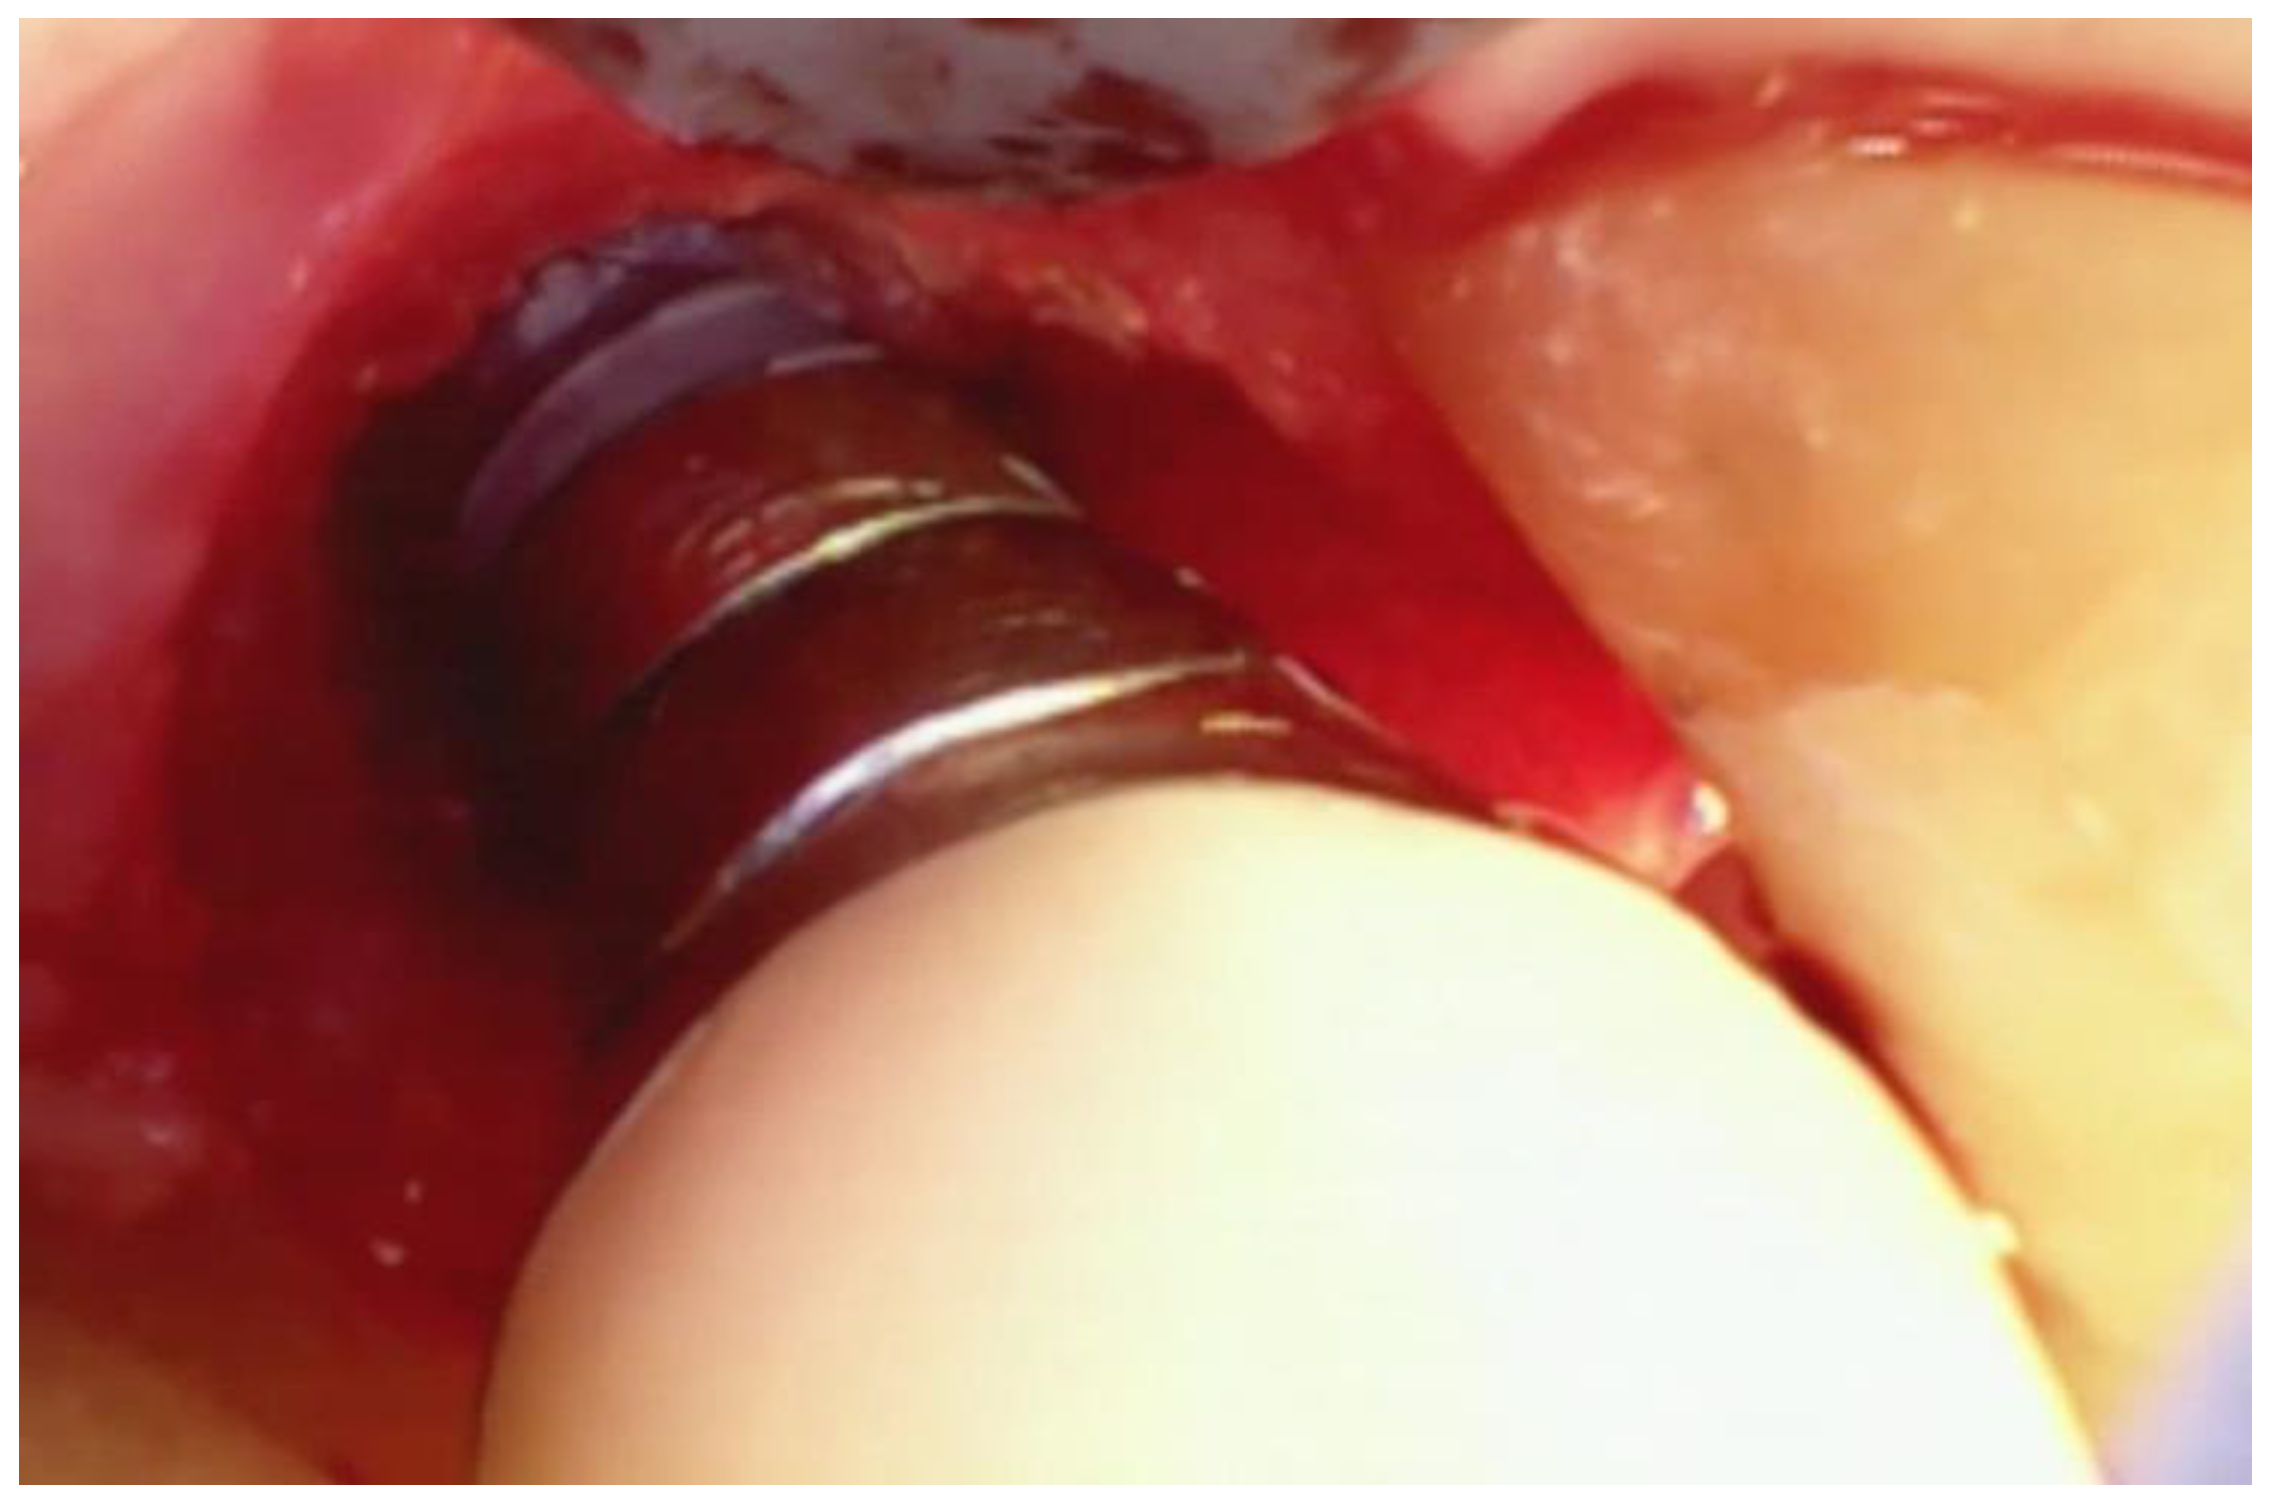

Suturing—A single vertical mattress suture placed at the base of the papilla is recommended for each site of VMIS. It is not necessary to use the papilla preservation suturing technique when the VMIS incision pattern is used. The suture should be placed in the thick area of tissue at the base of the papilla. No sutures are placed directly at the connecting incision between the two teeth. It has been determined that placing sutures in this thin tissue leads to greater post-operative recession. Once the single suture is placed at the base of the papilla, the incisions are primarily approximated by using finger pressure on a saline-soaked gauze. A closed surgical site is shown in Figure 5.

After the lesion is debrided of granulation tissue and the implant is cleaned with saline, DFDBA mixed with EMD is place in the bony defect. (Figure 9).

Figure 5. A Videoscope-Assisted Minimally Invasive Surgery (VMIS) palatal flap closed with a single vertical mattress suture at the base of the papilla. The edges of the incision in the papilla have been approximated with finger pressure only.

Figure 9. The bony lesion pictured in Figure 8 has been filled with particulate bone-grafting material mixed with EMD.